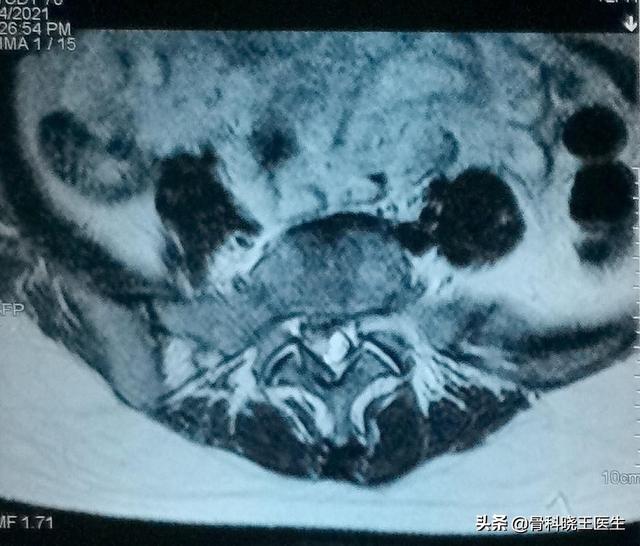

Les hernies discales légères à modérées peuvent très bien se rétablir, mais les hernies graves sont difficiles à traiter car une fois qu'une hernie grave s'est développée, cela signifie que le nucleus pulposus au centre du disque a traversé l'anneau fibreux au niveau du bord postérieur et même le ligament longitudinal postérieur, ce qui rend la guérison très difficile avec le temps. Ci-dessous, l'image tomodensitométrique d'un patient souffrant d'une hernie discale grave :

Il existe quatre états des disques intervertébraux : l'état normal, le disque bombé, la hernie discale et le prolapsus discal. Cet état correspond à une modification de l'état du nucleus pulposus due à la dégénérescence, à une contrainte, à une stimulation par le froid ou à un traumatisme. Si le nucleus pulposus ne fait qu'écraser anormalement l'annulus fibrosus et que l'annulus est simplement modifié dans sa forme mais non rompu, on parle de bombement discal ; si le nucleus pulposus coiffe l'annulus fibrosus et fait saillie hors de l'annulus fibrosus mais que la saillie a un diamètre inférieur à la brèche de l'annulus fibrosus, on parle de hernie ; si le nucleus pulposus fait saillie hors de l'annulus fibrosus et que la saillie a un diamètre supérieur à la brèche de l'annulus fibrosus, on parle d'hernie. Prolapsus.

Plus de 90 % des patients souffrant d'une hernie discale ne compriment pas la racine nerveuse. Les symptômes au niveau du bas du dos et des jambes sont dus à une inflammation des tissus mous de la région lombaire, à des adhérences et à un œdème qui irritent la racine nerveuse, et peuvent donc être soignés par un traitement conservateur. Seul un très petit nombre de hernies discales ou de prolapsus graves comprimeront la racine nerveuse et nécessiteront un traitement chirurgical. L'Association orthopédique chinoise souligne que les indications du traitement chirurgical sont au nombre de trois : douleur intense, le traitement conservateur est inefficace ; le patient est en position forcée, le traitement conservateur est inefficace ; les symptômes de la cauda equina, les dysfonctionnements urinaires et fécaux ou l'incontinence.